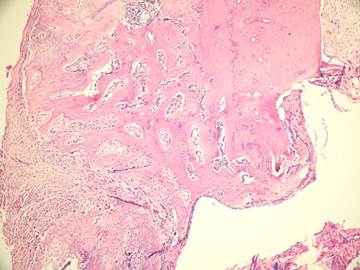

Figure 6

Inflammatory cells and new bone formation in control group (without irrigation, H&E

In the present study we evaluated the specimens in terms of new bone formation, presence of infection, necrosis and fibrosis Our study demonstrated significant difference regarding the necrosis values between control group (without irrigation) and the group irrigated with 25°C and 4°C saline (Figures 4-6). Necrosis was not observed in second and third groups. However copious saline irrigation was useful for cleaning the operation area from any remnants of the drill. It is thought that this can be an advantage for wound healing.